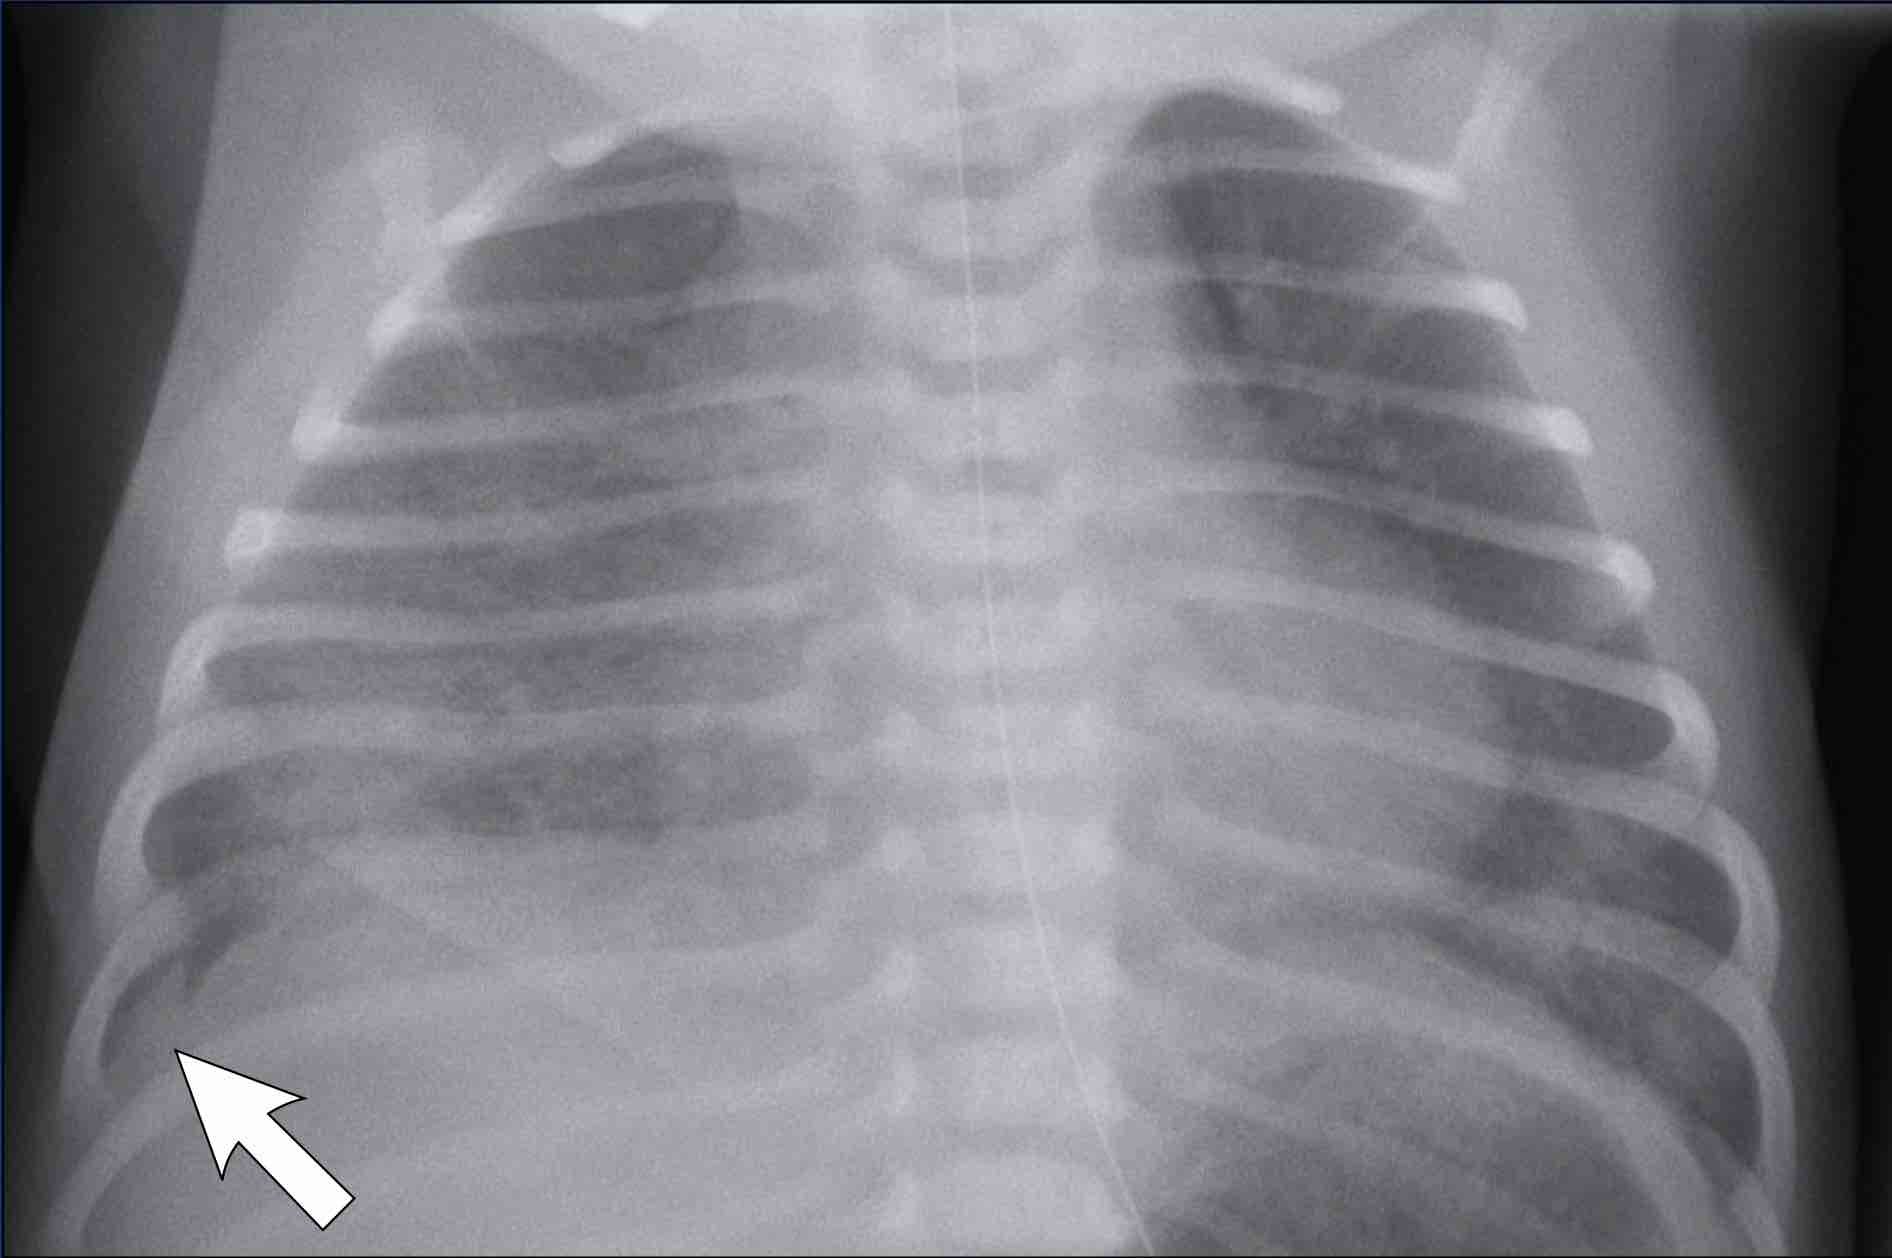

How To Read Neonatal Chest X Ray . basics of interpreting a neonatal chest radiograph. For evaluating the initial cause of respiratory distress. Neonatal unit, department of pediatrics,. the degree of rotation is best assessed by comparing the length of the anterior ribs visible on both sides. a specific finding on neonatal chest films is air leak tracking along the bronchi termed pulmonary interstitial emphysema (pie). (a) frontal chest radiograph at 3 months of age shows coarse interstitial opacities and overall mild hyperinflation. Standard chest radiograph is an anteroposterior. The specific reason why these radiographs are.

How To Read Neonatal Chest X Ray Standard chest radiograph is an anteroposterior. Neonatal unit, department of pediatrics,. For evaluating the initial cause of respiratory distress. basics of interpreting a neonatal chest radiograph. a specific finding on neonatal chest films is air leak tracking along the bronchi termed pulmonary interstitial emphysema (pie). the degree of rotation is best assessed by comparing the length of the anterior ribs visible on both sides. The specific reason why these radiographs are. Standard chest radiograph is an anteroposterior. (a) frontal chest radiograph at 3 months of age shows coarse interstitial opacities and overall mild hyperinflation.

Interpretation of Neonatal Chest Radiography How To Read Neonatal Chest X Ray Neonatal unit, department of pediatrics,. Standard chest radiograph is an anteroposterior. The specific reason why these radiographs are. the degree of rotation is best assessed by comparing the length of the anterior ribs visible on both sides. basics of interpreting a neonatal chest radiograph. (a) frontal chest radiograph at 3 months of age shows coarse interstitial opacities. How To Read Neonatal Chest X Ray.